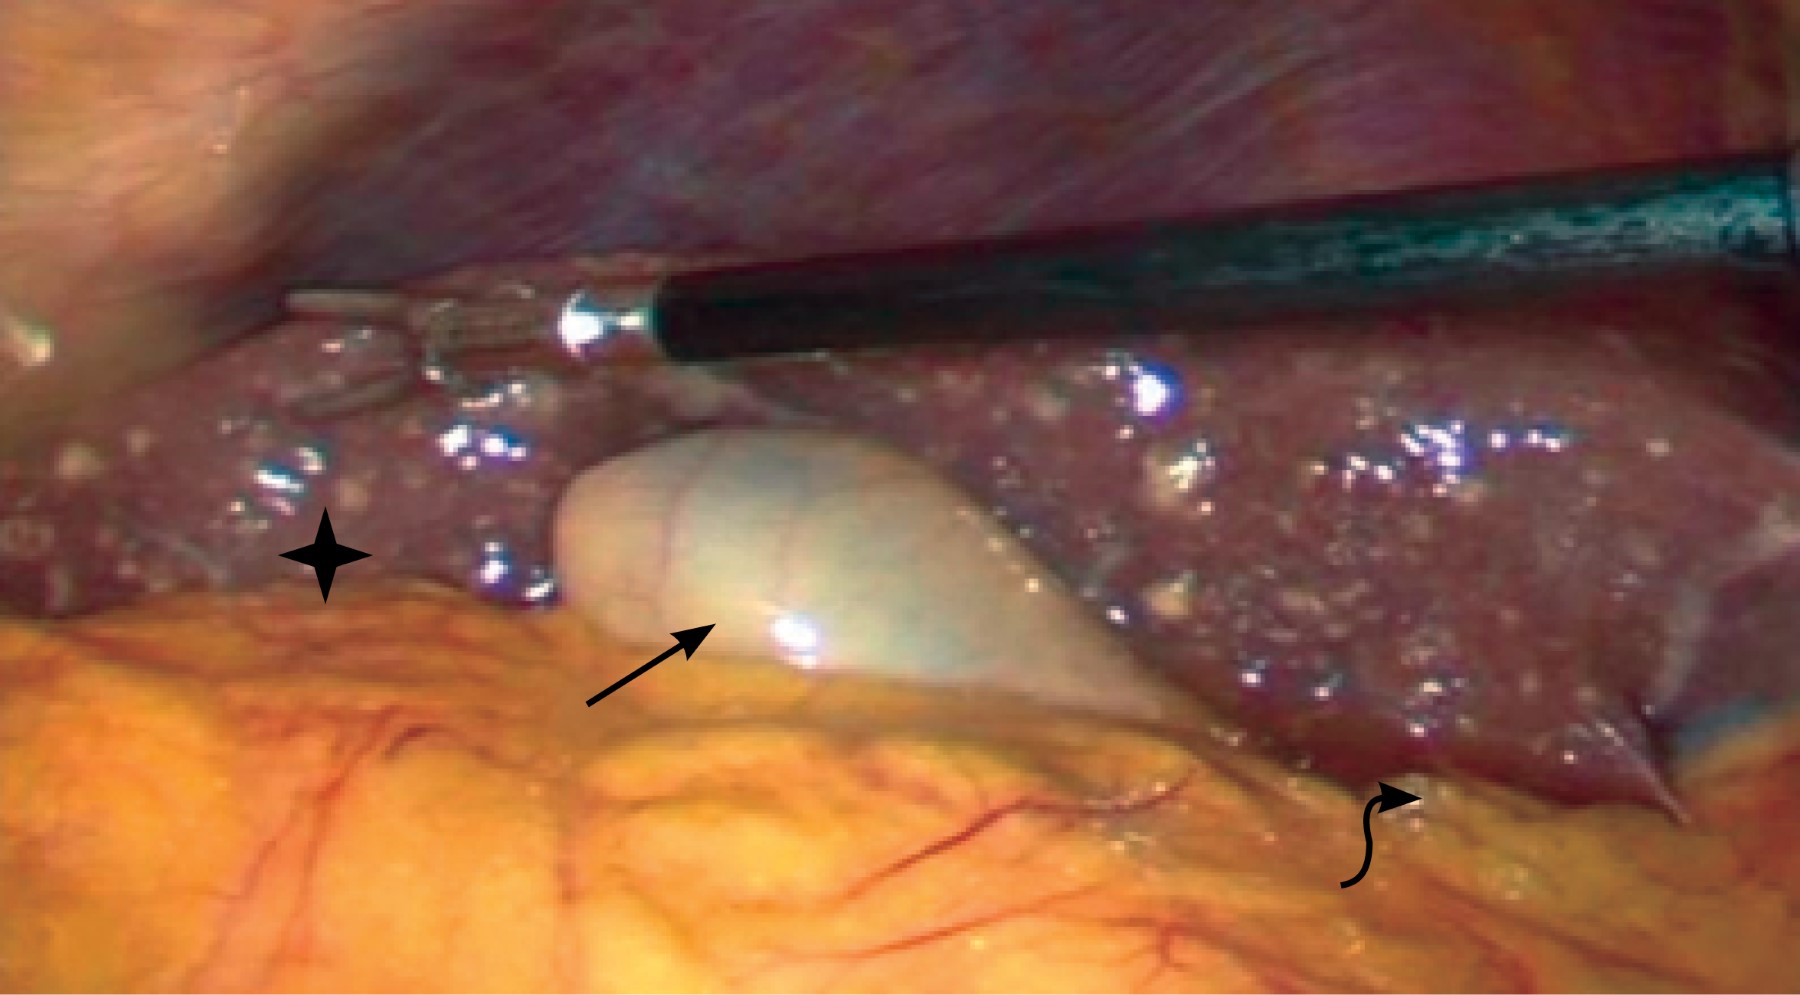

Se programó para laparoscopia diagnóstica teniendo los siguientes hallazgos: implantes hepáticos de primario desconocido, hepatomegalia, ascitis, vesícula biliar de pared delgada, sin cambios inflamatorios, por lo que se decide no efectuar colecistectomía al no tener indicación quirúrgica y ante los hallazgos mencionados con alta probabilidad de neoplasia. Se hizo toma de muestra de líquido peritoneal para estudio citológico y biopsia de implante hepático (Figura 3).